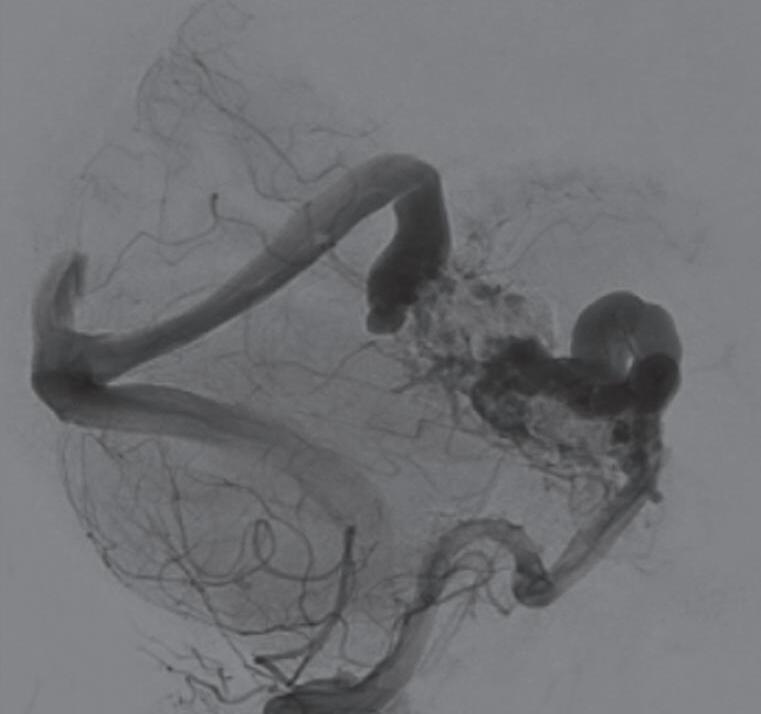

Com relação ao fluxo no interior do nidus, alguns autores classificam-nas em alto fluxo (Fig. 1-8) e baixo fluxo (Fig. 1-9). São consideradas de alto fluxo aquelas em que a opacificação após injeção de contraste ocorre apenas na malformação, em contrapartida, nas de baixo fluxo, ocorre opacificação da MAV e de outras artérias normais do mesmo território vascular. Exemplificando as lesões de alto fluxo temos as malformações arteriais, as malformações arteriovenosas e as fístulas arteriovenosas, enquanto as lesões de baixo fluxo são representadas pelas malformações venosas, linfáticas e capilares.25

Fig. 1-8. (a-c) RNM T1 com contraste, cortes sagital (a), coronal (b) e axial (c) demonstrando MAV não rota com nidus localizado no lobo occipital à esquerda (setas longas). (d) Arteriografia digital cerebral com injeção de contraste via carótida direita (AP) mostrando a contribuição da carótida direita na irrigação da MAV contralateral. (e,f) Com injeção de contraste via carótida esquerda, em Perfil e AP respectivamente, observa-se nidus compacto nutrido por ramos da artéria cerebral média à esquerda e a veia de drenagem precoce se dirigindo para o seio sagital superior. Projeções em AP (g) e em perfil (h) demonstrando a contribuição do sistema vertebrobasilar por meio de ramos distais da artéria cerebral posterior à esquerda e drenagem para os seios sagital superior e sigmoide à esquerda (setas curtas).